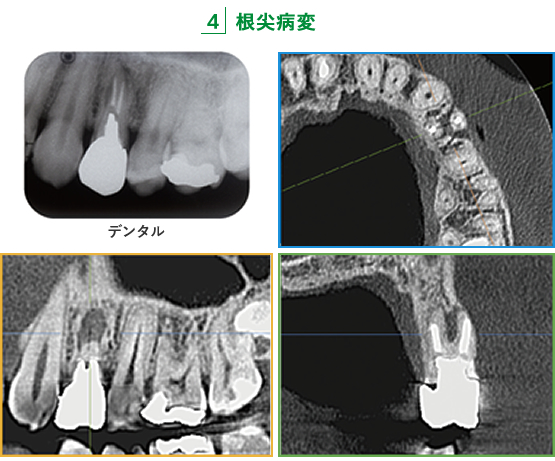

デンタルではわかりづらい根尖病変や樋状根が、3つの直交するCT画像で診ると明らかに把握できる。

根尖側半分が黒くなったデンタルをCT画像で診ると、重篤な骨欠損状態とわかる。